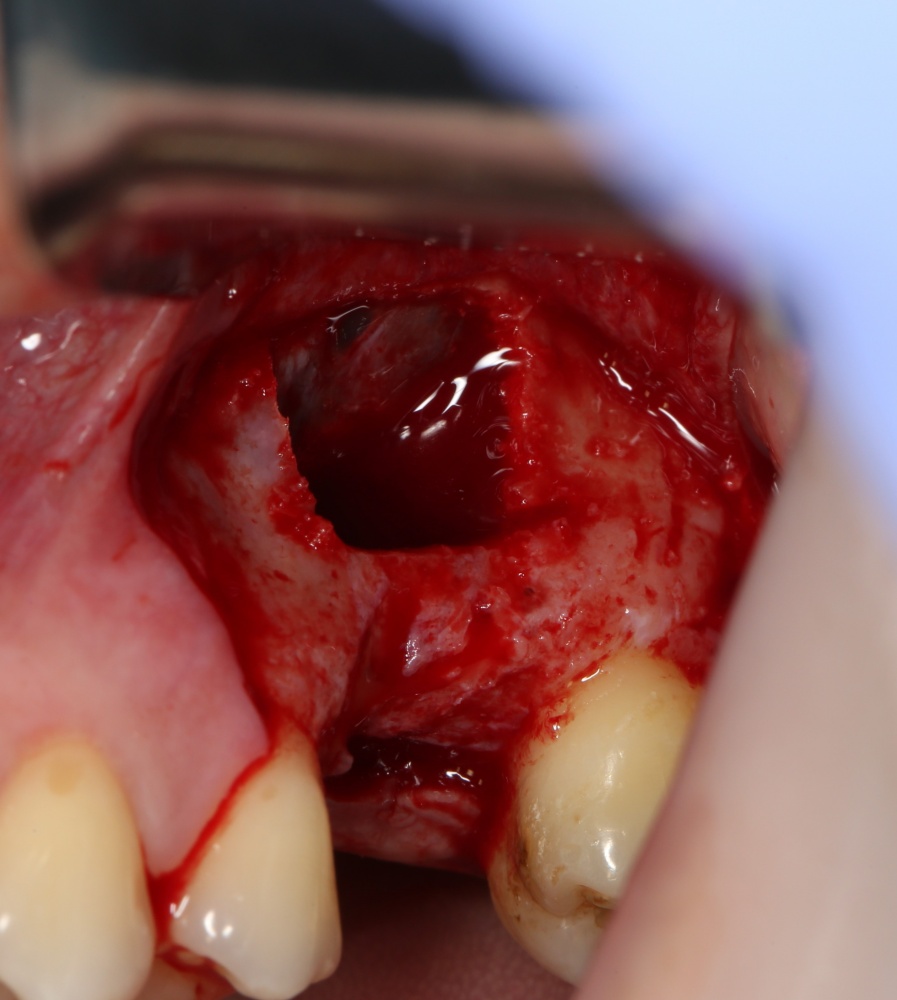

Простой синуслифтинг. Часть I.